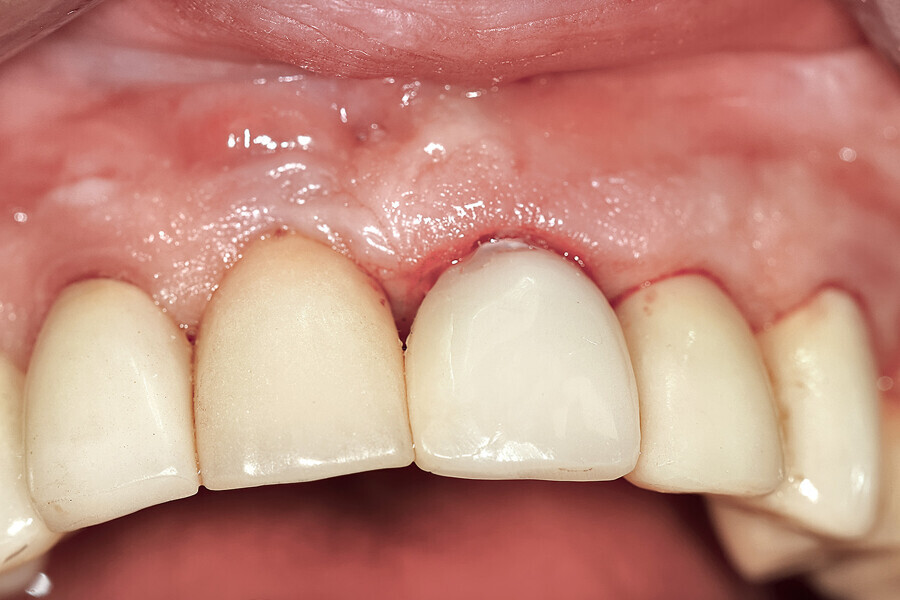

Fig. 12a: A post fracture presenting in the left central incisor, requiring extraction.

Fig. 12b: The occlusal view illustrated the cervical tissue volume and contours.